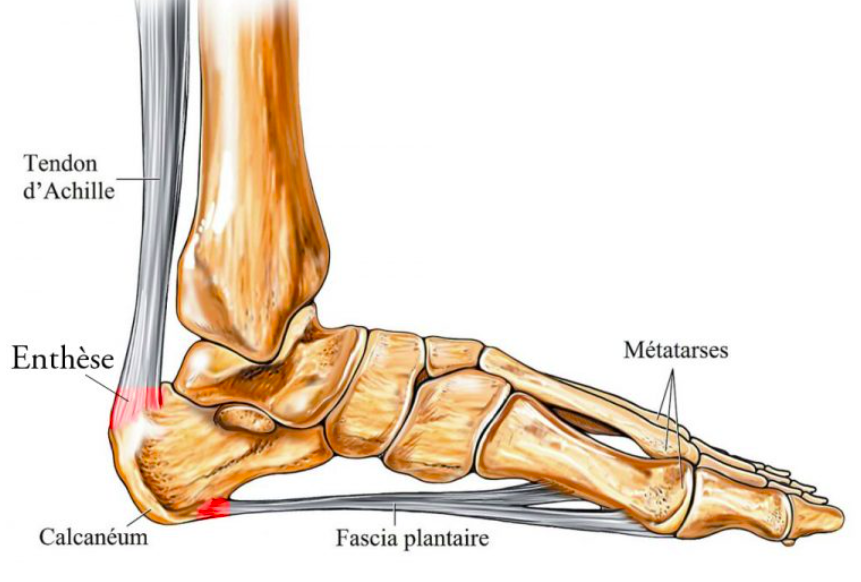

Talalgies

Les talalgies sont des douleurs au talon, qui se manifestent souvent pendant la marche ou les activités sportives. Elle peut être due à des causes mécaniques ou inflammatoires ou parfois, à une maladie.

Elles concernent les adultes et les enfants.

L’orthésiste prendra en compte le trouble statique du patient (pied plat, creux, genu velgum, recurvatum…). Selon l’examen clinique et l’origine de la talalgie, il réalisera les éléments nécessaires pour soulager son patient.

L’orthèse réduit la déformation et la douleur.

Fasciite plantaire & Aponévrosite plantaire

La fasciite plantaire est une inflammation du fascia plantaire, le ligament qui relie le talon aux orteils. Elle provoque une douleur vive sous le talon, particulièrement intense le matin au lever ou après une longue période d’immobilité. L’aponévrosite plantaire en est la forme chronique.

L’orthésiste réalise des semelles orthopédiques sur mesure permettant de décharger le fascia, corriger les défauts d’appui et réduire la tension à l’origine de l’inflammation. La semelle accompagne également la récupération en parallèle des séances de kinésithérapie.